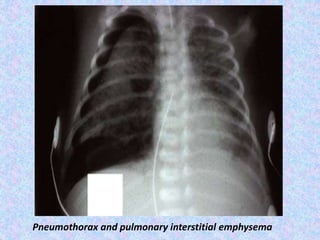

Pulmonary interstitial emphysema.

Pulmonary interstitial emphysema (PIE) refers to the abnormal location of air

within the pulmonary interstitium and lymphatics. It typically results from rupture

of overdistended alveoli following barotrauma in infants who have respiratory

distress syndrome. Interstitial emphysema can also occasionally be incidentally

detected in adults.

Radiographic features

Plain film - chest radiograph shows bubbles (round) or streaky (linear)

radioculencies in the interstitium radiating from the hilum . Affected segment is

often hyperexpanded and static in volume on multiple radiographs. Patients may

have pneumothorax, pneumomediastinum, or pneumopericardium in supine

patients, pneumomediastinum is evident by the sharp mediastinum sign

Pneumothorax and pulmonary interstitial emphysema